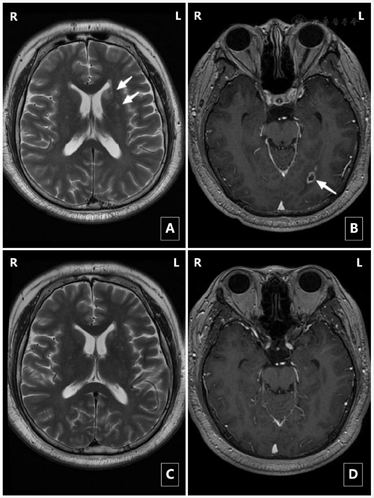

治疗前后颅脑MRI变化:

1.颅脑MRI平扫(2019年11月29日):未见异常。

2.颅脑MRI平扫+增强(2020年1月17日):与2019年12月27日比较,新增右侧额叶异常信号影,考虑感染性病变,左侧顶叶及邻近脑沟异常影较前未见明显变化,多考虑感染性病变,请结合临床。

3.颅脑MRI平扫(2020年8月25日):1.左侧顶枕叶局部脑沟变浅,皮髓质分解不清,较前未见明显变化(2020年3月18)2.左侧额顶枕叶皮层异常信号较前基本吸收;左侧基底节区异常信号,较前增多,请结合临床;3.左侧侧脑室后角旁异常强化信号,较前为新出现病灶。

4.颅脑MRI平扫(2021年1月28日):1.左侧基底节区及放射冠异常信号,较前片(2020年10月13日)变化不著,左侧侧脑室后角异常强化结节,较前体积明显缩小。

5.颅脑平扫+增强MRI(2021年4月10日):1.左侧侧脑室缺血灶;2.颅脑MR增强未见明显异常。

治疗前后头颅MRI对比图